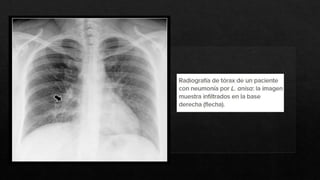

El término atípico para neumonía, fue utilizado

por primera vez en 1938, para referirse a un

grupo de neumonias, causadas por una bacteria

o patógenos no asociados usualmente a la

neumonia.